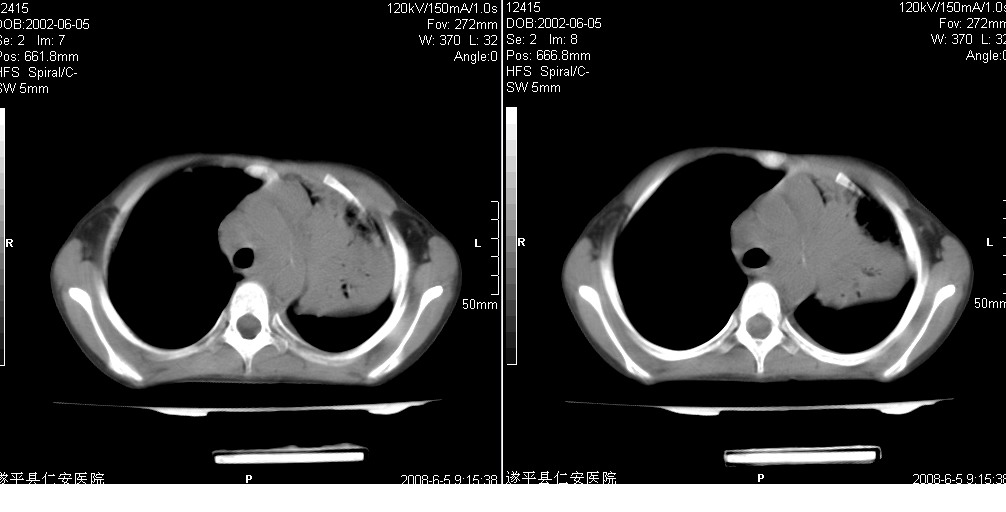

以下是引用xxhwh在2008-6-10 18:40:00的发言:[br]男,6岁,无规则发热一月余,体温在37.8——39度之间。一月前拍胸片示左上肺密度增高影,进行抗炎治疗8天,复查胸片未明显吸收。又改变抗菌素继续治疗半月,照胸片示病灶吸收不明显,行ct检查[br]征象:左上肺前段呈密实影,内可见支气管气像,远侧见絮状模糊影,中上纵隔左移。[br]意见:左上肺前段膨胀不全及感染,考虑为支气管异物或支气管内膜结核所致,[br]建议追问有无异物吸入史,行痰检及ppd检查